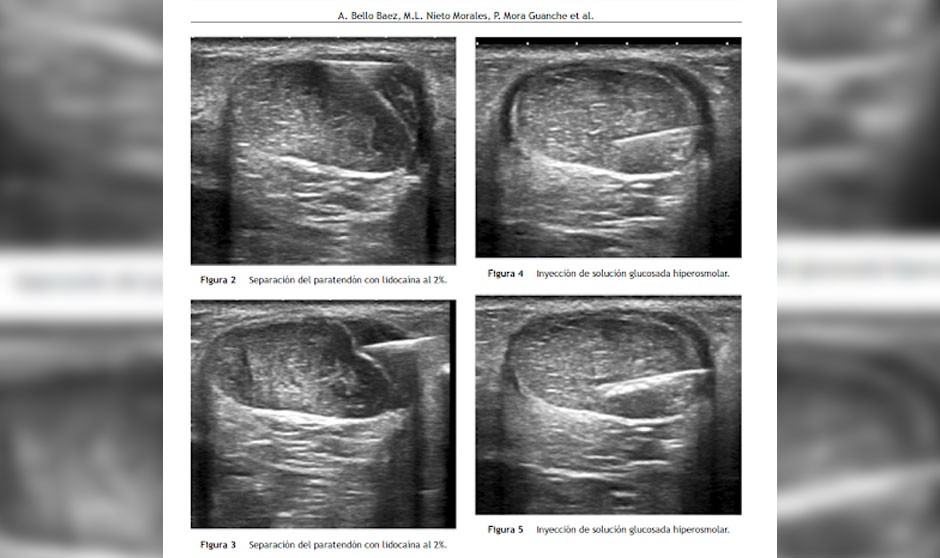

El tratamiento percutáneo de la tendinosis aquílea con proloterapia según el protocolo diseñado por Bello implica el uso de tres técnicas: hidrodisección del paratendón con lidocaína, punción seca de los focos de degeneración tendinosa -tendinosis- y por último la administración de solución irritante hiperosmolar a base de suero glucosado y anestesia dentro de los focos de tendinosis. Es una técnica segura, barata y prácticamente indolora que da lugar a una reducción progresiva de los nuevos vasos sanguíneos que han entrado en el tendón debido a la degeneración de éste, y lo que es más importante, reduce el número de terminaciones nerviosas que acompañan a esos vasos (Vasa nervorum) y que se cree que son los responsables últimos de despertar dolor en dichos pacientes. Esto provoca una disminución significativa de la percepción del dolor en reposo, con la actividad física diaria y durante el ejercicio moderado, que se mantienen con el tiempo.